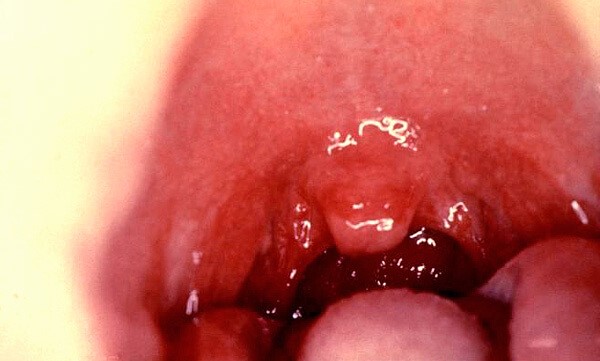

Гиперемия и отек миндалин при односторонней ангине также наблюдается исключительно, с одной стороны. На самом деле несмотря даже на явные симптомы, отличить атипичная у пациента ангина или что ни на есть обыкновенная, может, только опытный специалист. Если специалист опытный одного взгляда будет достаточно, чтобы разобраться, какая именно ангина мучает пациента и как ее лечить. Помните, атипичная ангина – это не та болезнь, при которой стоит заниматься самодиагностикой и самолечением, фатальной может стать даже небольшая ошибка неопытного терапевта.

Односторонняя ангина — это состояние, которое вызывает много вопросов и недоразумений. Многие люди считают, что ангина всегда проявляется симметрично, однако односторонняя боль в горле может быть не менее выраженной. Симптомы включают резкую боль при глотании, покраснение и отек одной миндалины, а также возможное увеличение лимфатических узлов с той же стороны. Часто пациенты путают это состояние с простудой или аллергией, что может привести к неправильному лечению. Важно помнить, что односторонняя ангина может быть вызвана различными инфекциями, включая бактериальные и вирусные. Поэтому при появлении подобных симптомов стоит обратиться к врачу для точной диагностики и назначения адекватной терапии. Не стоит недооценивать одностороннюю ангину, так как она может привести к серьезным осложнениям, если не будет своевременно лечена.

Еще один очень важный симптом атипичного тонзиллита, заключается в том, что эта ангина – протекает без высокой температуры. Проявляется односторонняя или атипичная ангина, в общем, то, как самый обыкновенный тонзиллит.

Хронический тонзиллит можно перепутать с лакунарной ангиной только из-за наличия характерных гнойных пробок в миндалинах, которые принимаются за растеки гноя. Эти пробки хорошо очерчены, редко сливаются в большие пятна. Зачастую пробки затвердевают и превращаются в так называемые камни в миндалинах.

Фолликулярная ангина — появляется мелкоточечный гнойный налет, лакунарная ангина — лакуны миндалин заполнены гноем, считается самой тяжелой формой.